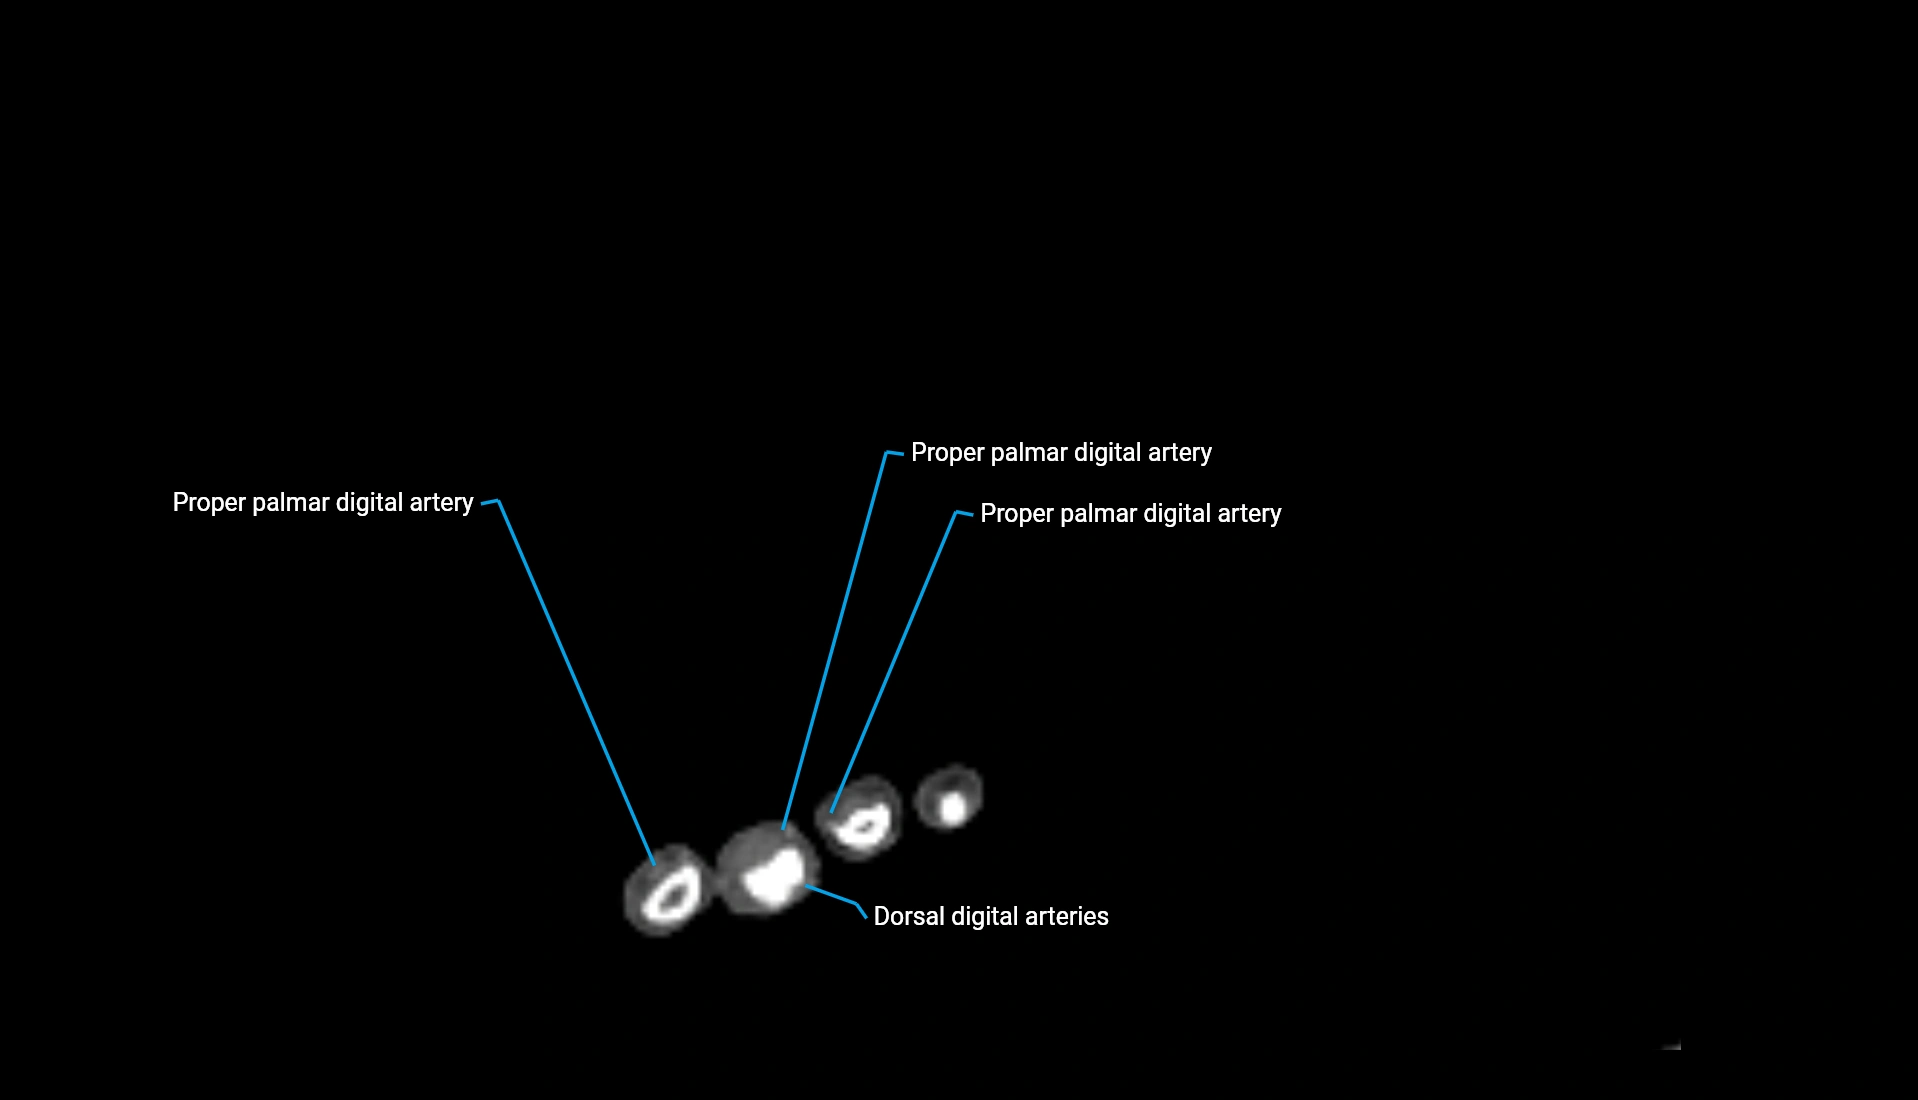

CT Appearance

Non-Contrast CT:

• Cortex: High-density, sharply defined

• Subchondral bone: Dense cancellous matrix

• Articular surface: Smooth concave contour articulating with the capitellum

• Excellent for evaluating bone integrity, alignment, and subtle fractures